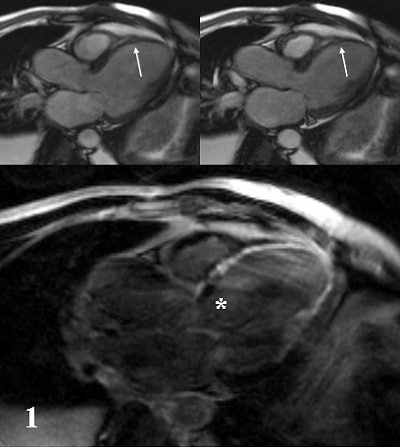

| Two midventricular images at 10 and 40 μg/kg/min. of dobutamine. The arrow (at 40 μg) indicates absence of septal wall thickening, which is indicative of inducible myocardial ischemia. Image courtesy of Dr. Caroline Janssen. |

![]() |

| A 42-year-old male patient after large myocardial infarction. Top, diastolic (left) and systolic (right) TrueFISP Cine images in LVOT orientation. Arrows show a large akinetic area in the anteroseptal wall. Bottom, IR-TurboFLASH image done 10 minutes after administration of gadolinium. The bright area shows transmural infarction (late enhancement) of the anteroseptal, apical and inferolateral wall. Asterisk shows a small akinetic area without late enhancement in the basal anteroseptal wall. |